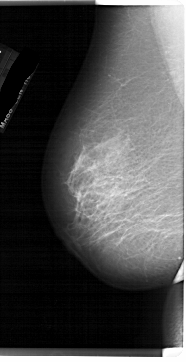

LEFT_CC LINES 6871 PIXELS_PER_LINE 3496 BITS_PER_PIXEL 12 RESOLUTION 43.5 NON_OVERLAY